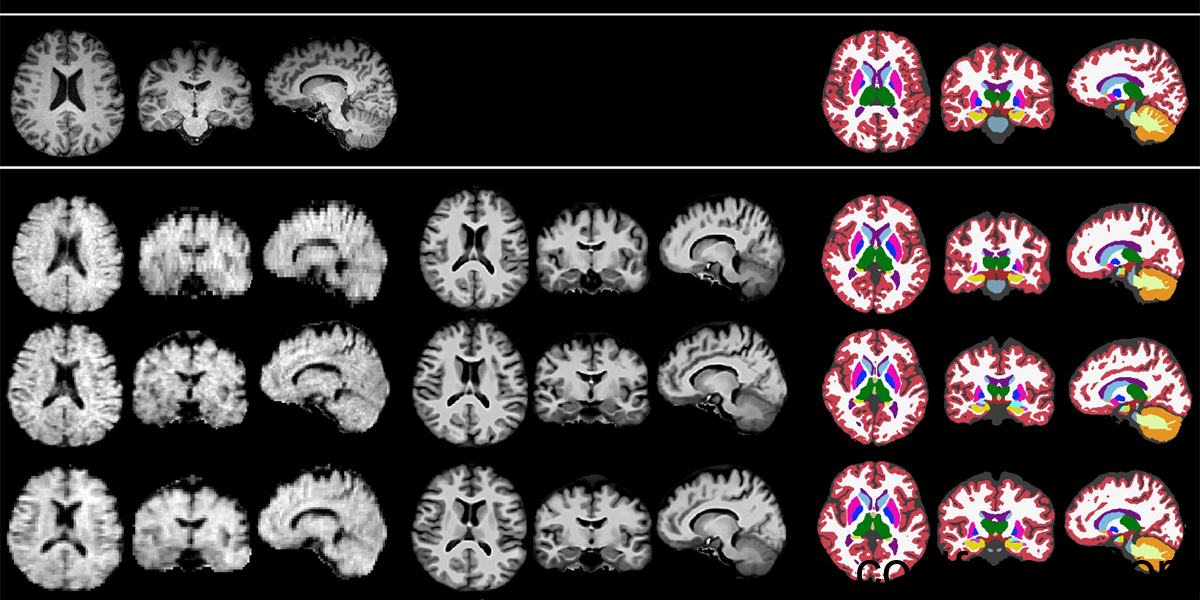

Images from high-field MRI machines (top row) are high quality enough to be directly assessed by automated tools such as SynthSeg. To do the same with images taken by low-field machines (bottom rows), researchers first used the machine learning program LF-SynthSR to improve their resolution. Credit: Sorby-Adams et al.; See licensing information below

On top of increasing the quality of images acquired by low-field MRI, the researchers also developed fully automated programs to identify different regions of the brain and then calculate the volume of parts of interest. In the new work, the authors cranked up the difficulty by deploying low-field MRI and their machine learning tools in a larger number of people, including many patients with Alzheimer’s disease or mild cognitive impairment (MCI).

In particular, they used their automated approach to calculate the size of the hippocampus and lateral ventricle – regions of the brain that are often altered in Alzheimer’s disease. They also used the system to identify and measure lesions in the brain, called white matter hyperintensities, also linked to Alzheimer’s. Tracking changes in these regions is useful for both diagnosing and monitoring the progression of degenerative conditions.

Throughout experiments across nearly 100 subjects, the results from their AI-enhanced, low-field MRI system were on par with measurements taken with conventional, high-field machines. The authors showed that both methods could distinguish the brains of subjects with Alzheimer’s disease or MCI from those that were healthy at a similar level of accuracy.